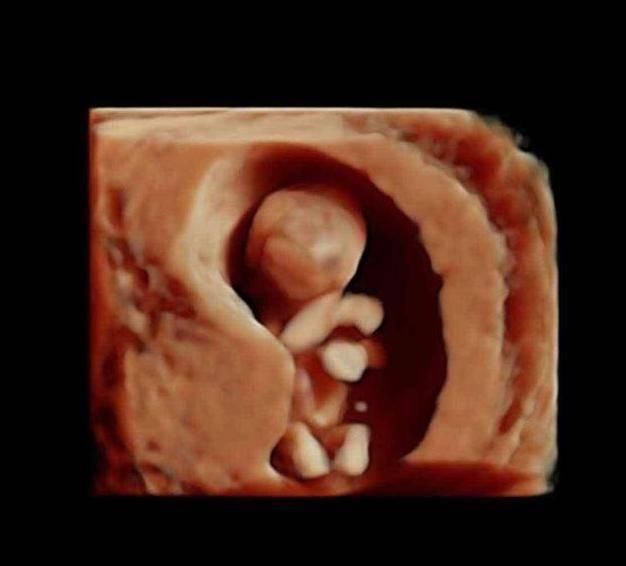

进入第10周,胎儿的发育更细致了,比如眼睛和眼睑已经融合,眼睛清晰可见,手臂和胳膊等都很清楚,此时的胎儿开始发阿玉生殖器官,不过肉眼是看不出来性别的。

进入12周,胎儿开始在羊水中又动了,骨骼发育开始坚硬,宝宝的四肢开始做很多动作,肾脏开始分泌尿液,肝脏开始分泌胆汁,维持生命的重要器官更多地开始工作了。

13-15周,胎儿的眼睛开始转动,大脑也在飞速地发育,胎儿的小脸已经和成人差不多了,神经元开始增多,条件反射也开始增加,胎儿身材比例越来越合理了。